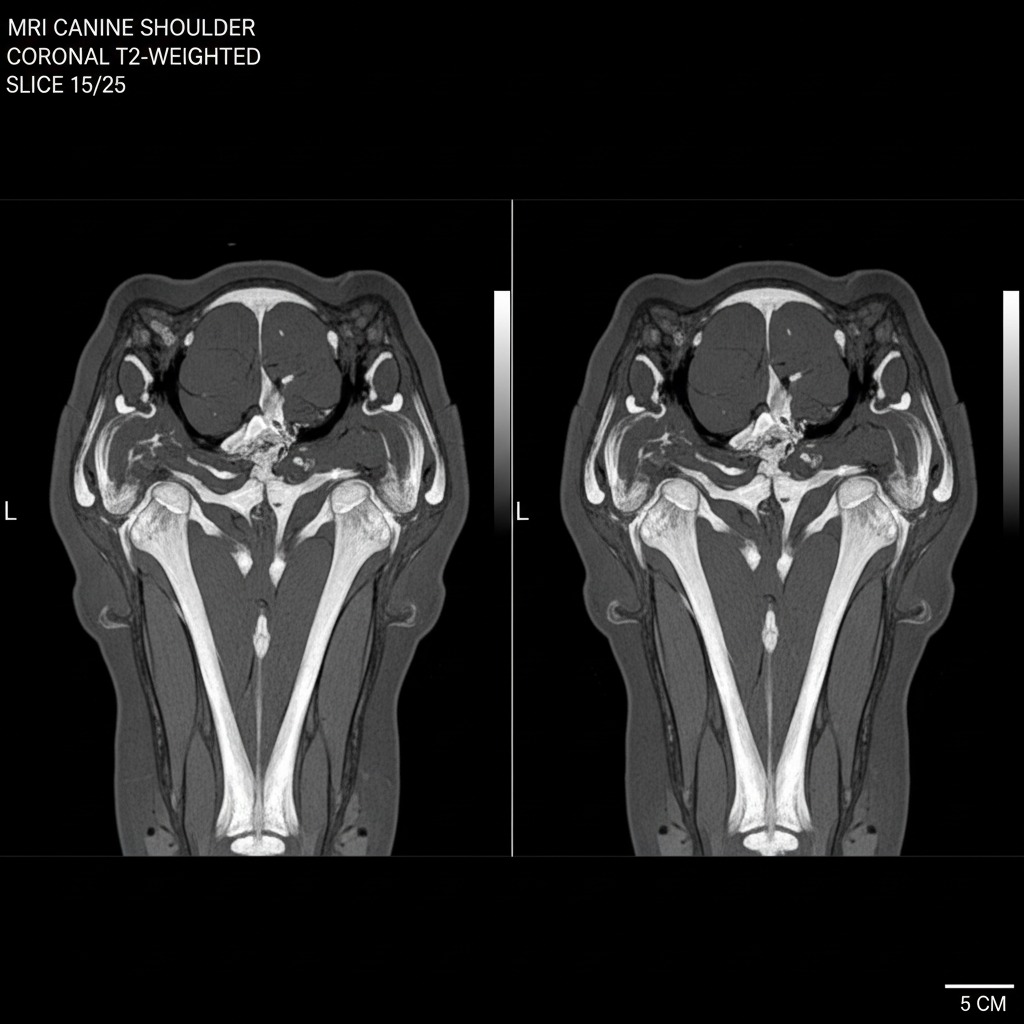

Discover Animalgo, the specialized AI solutions for canine MSK diagnostics (musculoskeletal). The goal is the focused development of AI solutions for the spine, knee, hip, and shoulder in dogs.

Innovative AI-powered Canine MSK Diagnostics

Experience cutting-edge technologies for precise analysis of the spine, knee, hip, and shoulder in dogs that promote health and optimize therapies.

We analyze your dog’s spine, knees, hips, and shoulders using advanced AI technology.